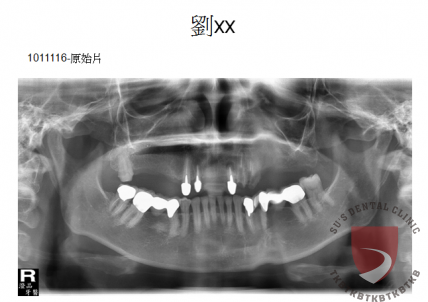

全口重建劉xx

成效因人而異,須遵從專業醫師指引